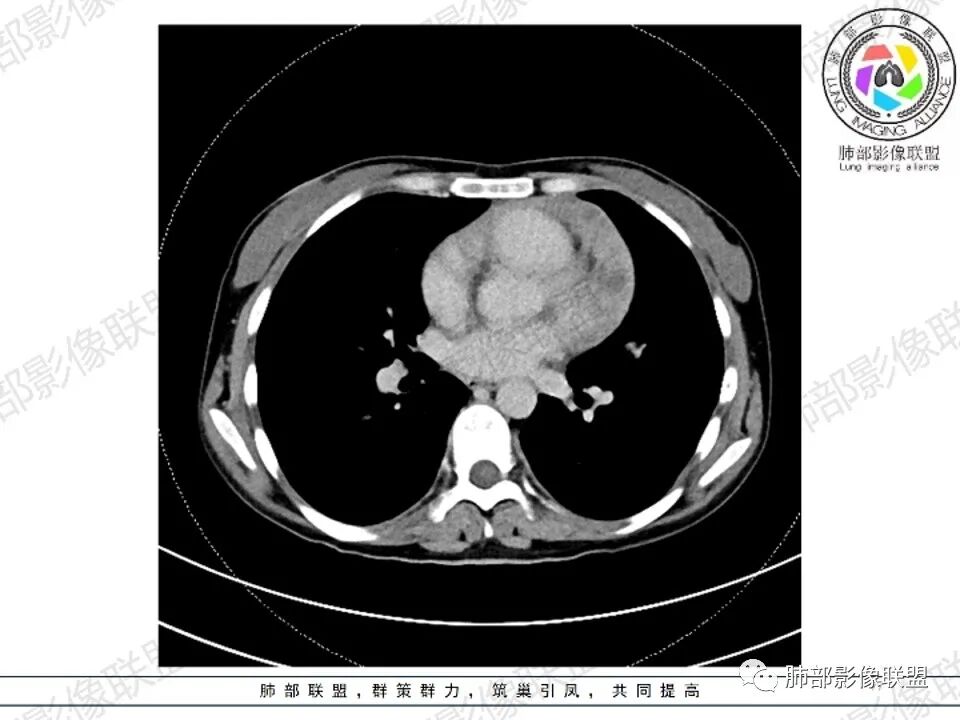

纵隔多发结节堆积 塑型生长  质软 边界不清 强化不均  双侧腋窝淋巴结肿大

年轻女性,贫血,CT示前纵隔团片状软组织占位,多结节堆积感,塑形生长,边界欠清,包绕大血管及心包,增强明显不均匀强化,内见血管漂浮。纵隔4R,5,7区及双侧腋窝多发肿大淋巴结,综合考虑为淋巴瘤可能

病灶两叶,相对独立,中央相连

整体还是胸腺的形态

边缘平直为主,稍膨隆,但是无明显的局限性凸起

囊变区域弥漫,大部分直达壁,分界不清,部分分界清楚

内部血管走形自然

女,27,间断头晕、乏力3年,左眼视物模糊2月。贫血。胸部CT:前纵隔不规则肿块,多结节融合,边界不清,沿主动脉及肺动脉间隙生长,平扫密度欠均匀,增强扫描可见多发低密度坏死,纵隔血管供血穿行,腋窝多发大小不等淋巴结肿大。考虑恶性病变,胸腺癌?肉瘤?淋巴瘤?鉴别胸腺瘤、结节病等。

2.影像显示前纵隔不规则块状影,依势贴附心脏大血管旁,密度不均,边界不甚清楚,有结节融合感。

3.病灶轻度不均匀强化,可见血管穿行,散在液性低密度区。

1.年轻女性,前纵隔不规则块状影,密度不均,边界不甚清楚,有结节融合感,轻度不均匀强化,可见血管穿行,最常见最符合的无疑是淋巴瘤!

3、影像学表现:显著肿大强化的淋巴结,常局限性分布;当患者无或仅轻微症状,纵隔内和腹膜后出现单个慢性巨大肿块,CT平扫示肿块边缘清楚,实质密度均匀,尤其是肿块呈显著强化和邻近大血管一致时,提示本病的可能。即使实质密度不均匀,中心液化坏死,但实质部分呈显著强化,与邻近大血管相似时,在鉴别诊断中仍然要考虑到本病的可能。